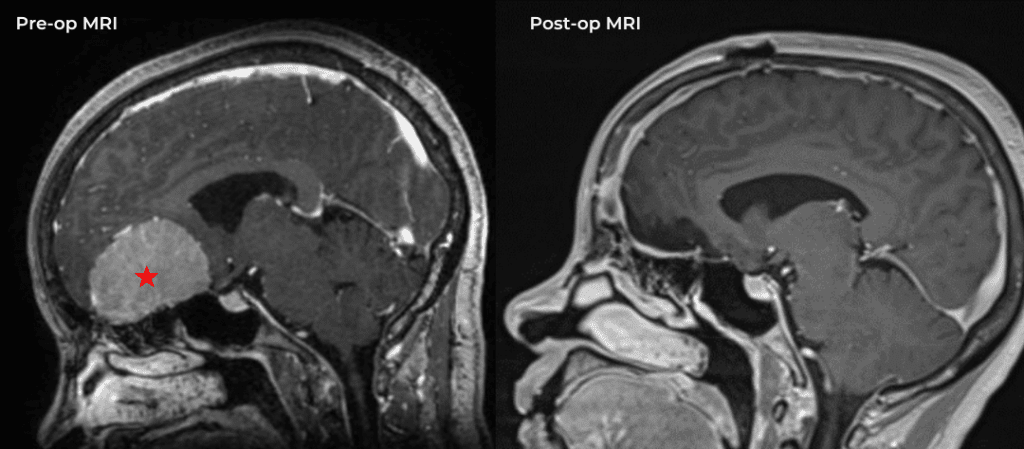

Brain:

74 Year Old Woman with Occipital Headaches

Author: Michael Brisman M.D., F.A.C.S., Read More!